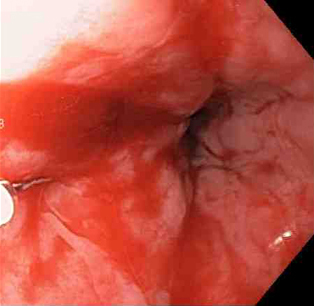

[Figure caption and citation for the preceding image starts]: Mallory-Weiss tear after adrenaline injection (the bleeding has stopped, allowing better visualisation of the lesion)From the collection of Juan Carlos Munoz, MD, University of Florida [Citation ends].

[Figure caption and citation for the preceding image starts]: Adrenaline is injected locally around the site of the Mallory-Weiss tearFrom the collection of Juan Carlos Munoz, MD, University of Florida [Citation ends].